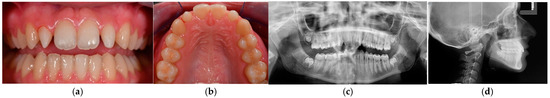

2.2. Case 2

2.2.1. Patient Presentation

2.2.2. Clinical Findings

2.2.3. Diagnosis and Assessment

2.2.4. Intervention Types Considered

2.2.5. Therapeutic Intervention